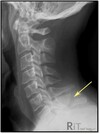

What pathology is present?

Hangmans fracture

What is the mechanism of injury for a Hangmans fracture?

Acute hyperextension of the head on the neck

126

# T/F A hangmans fracture results in anterior subluxation of C2 on C3

What part of the vertebra is fractured in a hangmans fracture?

Both pedicles of C2